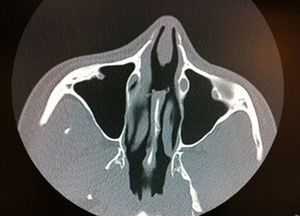

Evaluation by the ear, nose, and throat (ENT) department found no anomalies in any of the following tests: blood tests including serology for syphilis, angiotensin-converting enzyme, antinuclear antibodies, anti-DNA, antineutrophil cytoplasmic antibodies (ANCAs) with a cytoplasmic distribution, and ANCAs with a perinuclear distribution; urine toxicology; and bacterial cultures (all negative). Rhinoscopy showed septal perforation with invasive borders. Computed tomography showed septal perforation but no signs of disease in the sinuses or other bone structures (Fig. 1). Six punch biopsies were performed and histologic examination showed an ulcerated mucosa with fibrosis and inflammation of the chorion; there was no evidence of vasculitis, thrombosis, granulomas, or atypia (Fig. 2). The patient was prescribed topical and oral antibiotics for 18 months during follow-up at the ENT department but showed little improvement. A septal button was subsequently fitted but was removed 15 days later due to patient intolerance.